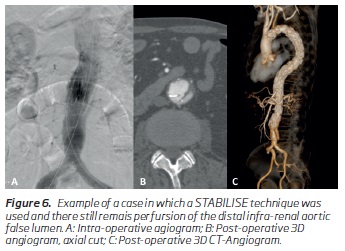

In some patients, even following placement of a distal bare-metal stent, like the STABILISE technique, false lumen perfusion and true lumen compression at the very distal aorta still persists due to distal communicating tears(6) (Figure 6). In these patients, if there are still signs of infra-renal aortic or iliac compression/occlusion or distal thrombosis of the false lumen, a CERAB may be performed in order to expand the true lumen and occlude these distal communicating tears.